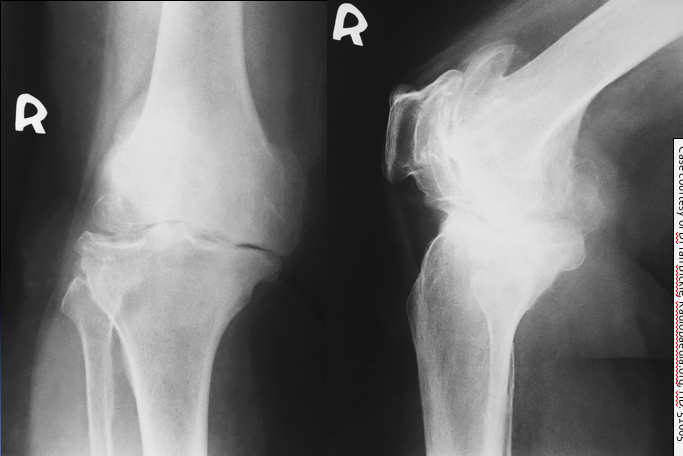

This 75 year old woman presented with difficulty walking and knee pain. How would you describe these X-rays?

A 30 year old man presented to the ED with left knee pain after a cycling accident.

On examination there was no deformity, but it was painful for him to weight-bear. Movements of his knee were painful, and this limited his movements.